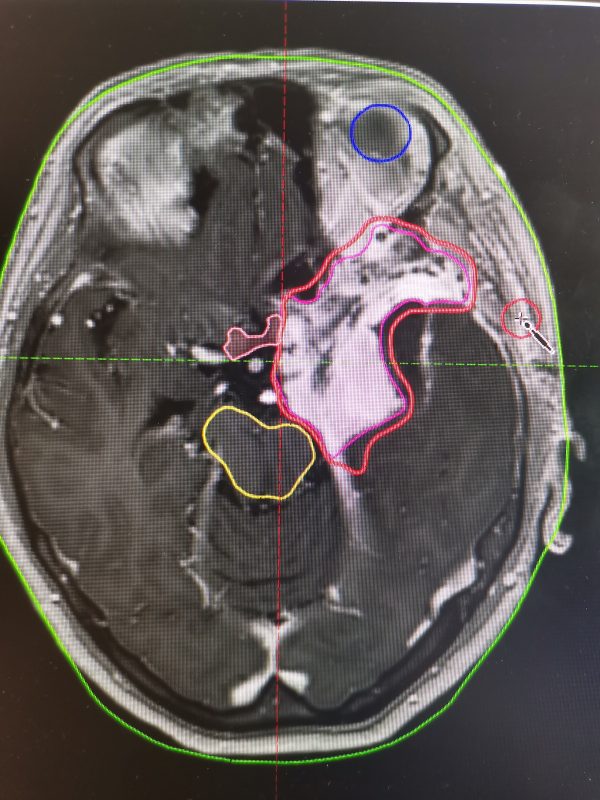

Особое значение современные технологии имеют при лечении опухолей головного мозга. Так, в ряде случаев, например при доброкачественных новообразованиях оболочек головного мозга, хирургическое вмешательство сопряжено с высоким риском утраты зрения и снижения слуха. В подобных клинических ситуациях единственным безопасным и радикальным методом лечения является высокотехнологичная лучевая терапия (фото).

В новом радиотерапевтическом корпусе Воронежского областного научно-клинического онкологического центра лучевая терапия проводится на линейном ускорителе Varian TrueBeam. Данный аппарат обеспечивает высокоточную доставку дозы непосредственно в опухолевый очаг при максимальной защите критически важных структур — органов зрения, слуха и головного мозга.

Применение современных методик лучевой терапии позволяет не только добиться высоких онкологических результатов, но и сохранить качество жизни пациентов, минимизировав риск таких осложнений, как снижение слуха, зрения и когнитивных функций.